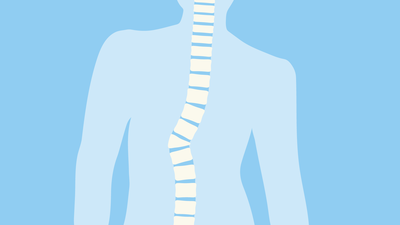

Eine Skoliose ist eine dreidimensionale Verkrümmung der Wirbelsäule. Die Krümmung in der Frontalansicht beträgt dabei laut Definition mehr als 10 Grad nach Cobb (siehe unten). Zusätzlich findet sich eine Rotation der Wirbelkörper, welche unterschiedlich stark ausgeprägt sein kann.

- C-förmig

- S-förmig